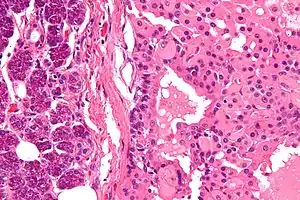

| Micrograph of a parotid gland oncocytoma (right of image). Normal parotid gland is also present (left of image). H&E stain. | |

Salivary gland oncocytoma

The salivary gland oncocytoma is a well-circumscribed, benign neoplastic growth also called an oxyphilic adenoma. It comprises about 1% of all salivary gland tumors. The histopathology is marked by sheets of large swollen polyhedral epithelial oncocytes, which are granular acidophilic parotid cells with centrally located nuclei. The granules are created by the mitochondria.